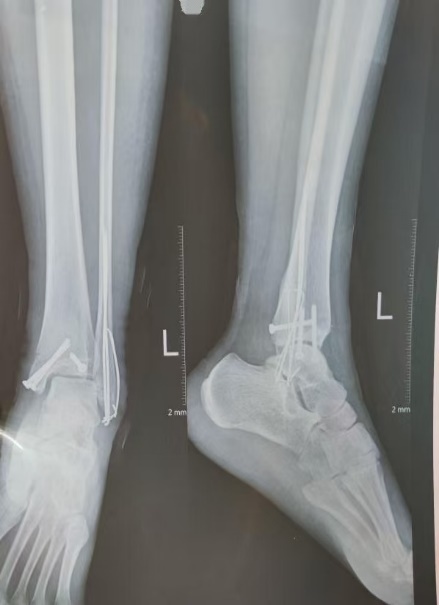

下肢骨折术后如何“走”出迷茫?

下肢骨折在日常生活中颇为常见,其成因繁杂多样,无论是意外事故,还是运动过程中的不慎损伤等,都有可能导致下肢骨折情况的发生。术后康复这一环节对于下肢功能能否顺利恢复以及生活质量能否有效提升,有着至关重要的影响,可谓举足轻重。本文将为您介绍下肢骨折术后康复的相关知识,帮助您更好地了解这一重要阶段,助力康复之路。